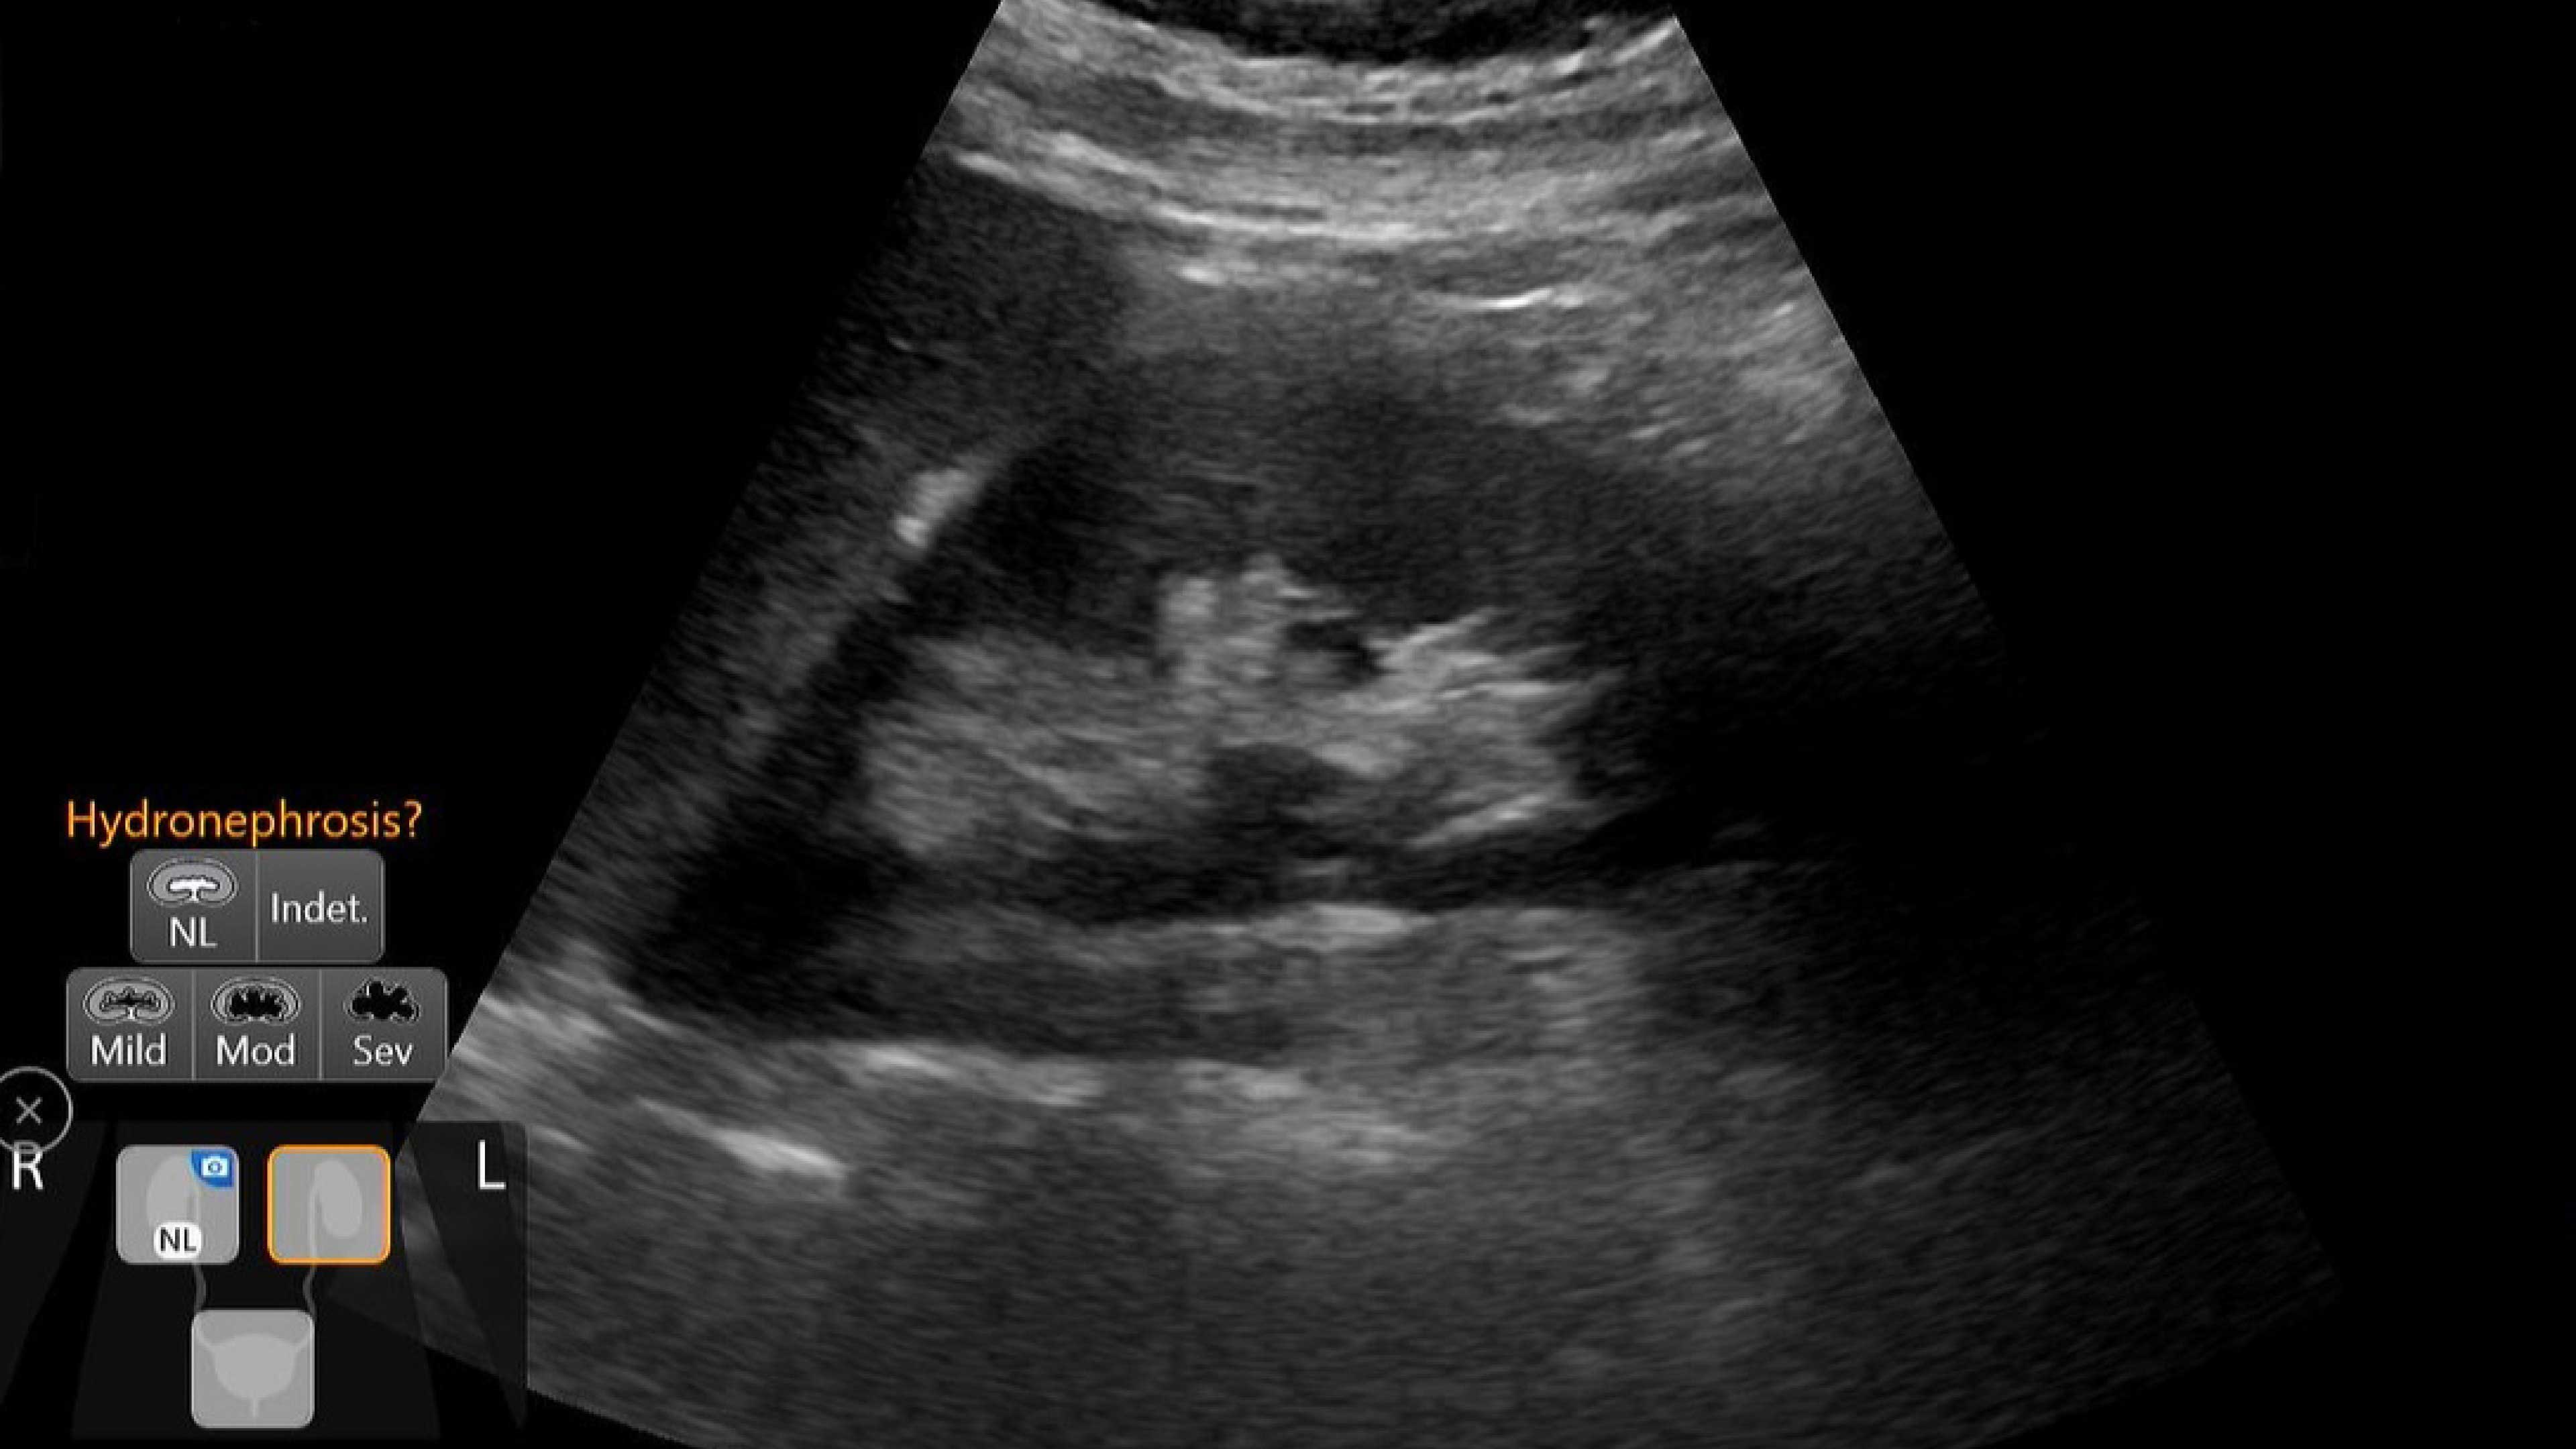

Critical care

Enables on-the-spot visual confirmation, aiding the team in decision-making and collaboration on complex cases.